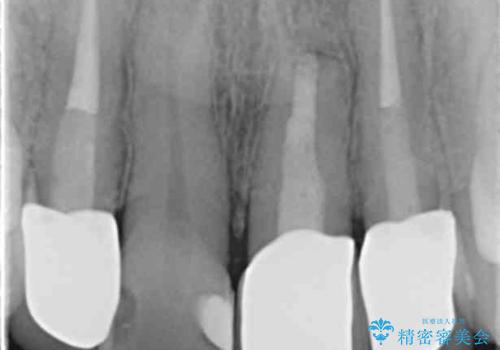

- 前歯のクラウンの歯肉の位置が年々変化し、歯ぐきのフチが黒くなってしまった、綺麗にしたいと希望されて来院されました。

装着されているセラミッククラウンを除去したのち、現在の歯ぐきのラインにしっかりと合う精度の高いオールセラミッククラウンを作製していきます。